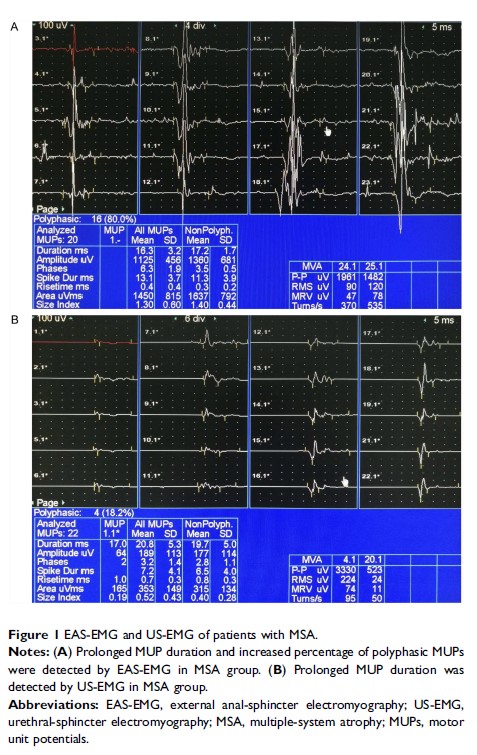

Original Research

外部肛门和尿道括约肌肌电图对帕金森叠加综合征多系统萎缩的鉴别诊断

- 作者:Feng Qiu, Kunyu Wang, Tingting Li, Dandan Song, Zhiwei Wang, Hailing Zhang, Jianguo Liu, Ming Ren, Xiaokun Qi

- 期刊:Neuropsychiatric Disease and Treatment